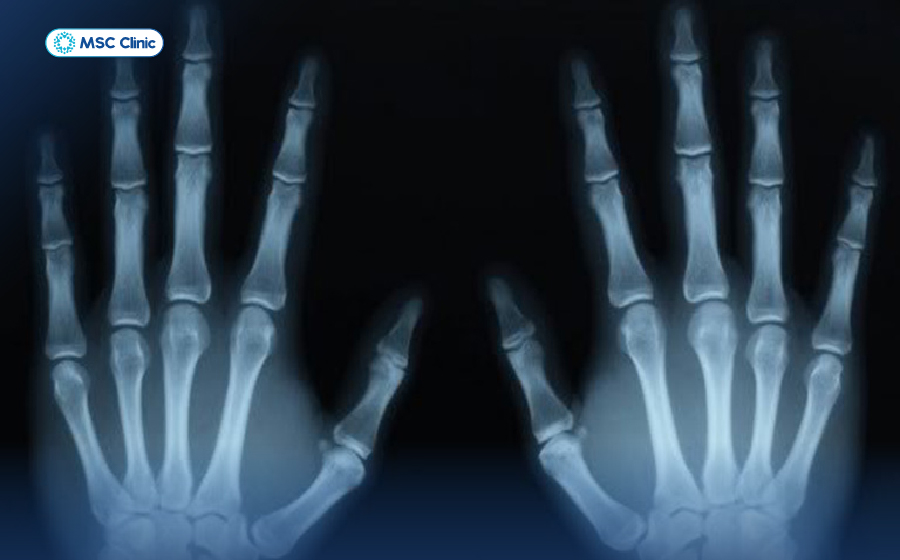

Người bệnh có thể chẩn đoán viêm khớp dạng thấp qua hình ảnh X – quang